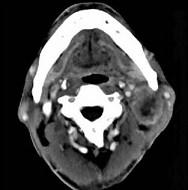

问题 65岁男性,吸烟史30余年,近半年来颈部出现疼痛性肿块,CT扫描如图所示,请选择最可能诊断()

选项 A.淋巴结核 B.血管瘤 C.神经鞘瘤 D.淋巴结转移瘤 E.软组织脓肿

答案 D